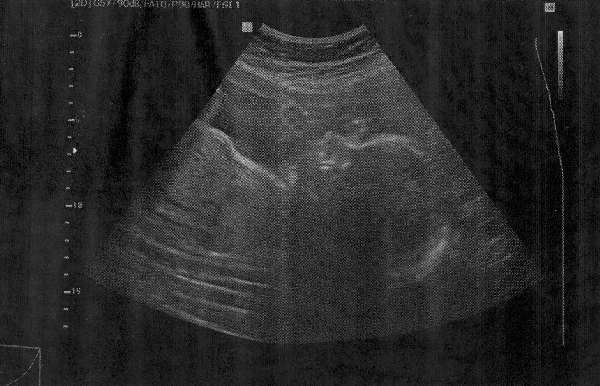

Mako, nagyon nagy gratula!!! Gyönyörűséges a 2 picúr és külön petezsákban, de jó!